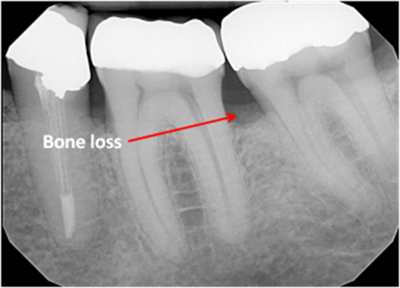

• Bone loss

bone loss